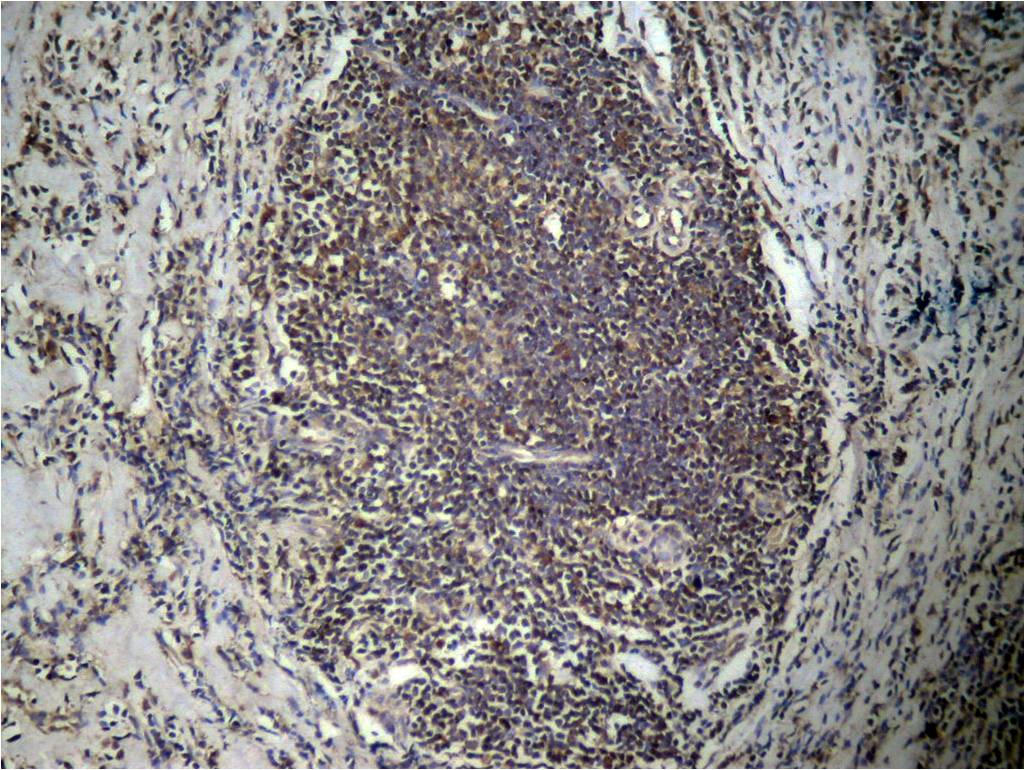

Product Image

| IHC | 1/50-1/100 |

| Immunogen | Peptide sequence around Di-Methylation site of lysine 27(A-R-K(di-methyl)-S-A) derived from Human Histone H3. |